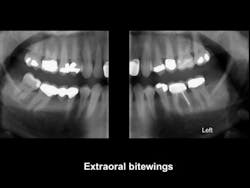

Currently, many dentists do not have digital panoramic devices. I suggest that this technology is one of the most important investments that you can make. Numerous brands are available. Look at them carefully, and purchase the brand that best fits your practice needs. Make sure that the device you purchase can be upgraded when you desire to incorporate cone beam or extraoral bitewing radiology into your practice (figure 1).

Figure 1: Extraoral bitewings provide excellent screening images of the maxillary and mandibular arches from third molar to lateral incisor with minimal overlap. They are available as an addition to most digital panoramic devices.